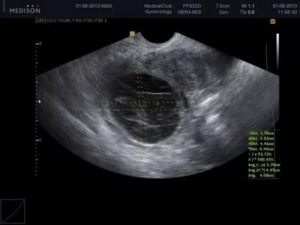

Во время гинекологического осмотра врач может найти уплотнения, образовавшиеся в области придатков. Определить наличие кист во время беременности можно на УЗИ с использованием вагинального датчика.

- УЗИ брюшной полости показывает объемные эхогенные новообразования и дает оценку их размерам. Во время беременности на УЗИ достаточно сложно определить желтое тело, из-за его небольшой величины;

- отличить кистозное желтое тело от опухолей яичников поможет цветовая допплерография;